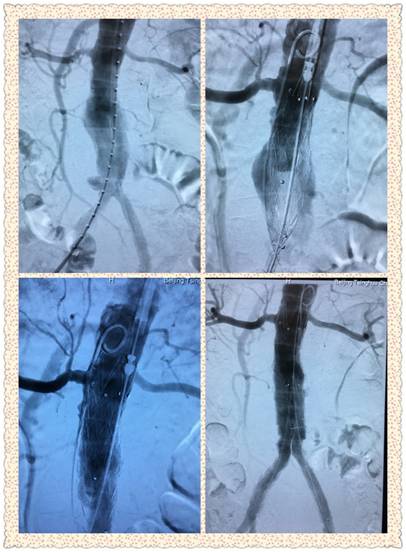

腹主动脉瘤成功修复(左上术前,右下术后)

这次张老手术中所使用的支架是目前国际上最先进的Endurant II主动脉覆膜支架。这一型号的支架更加柔顺,与腹主动脉内壁贴合更好,手术成功率更高,手术成功后支架与人体融为一体,可以在人体内一直使用而无需担心老化问题。

吴巍巍主任、赵俊来医师、曹战江医师在术中精准定位并释放支架